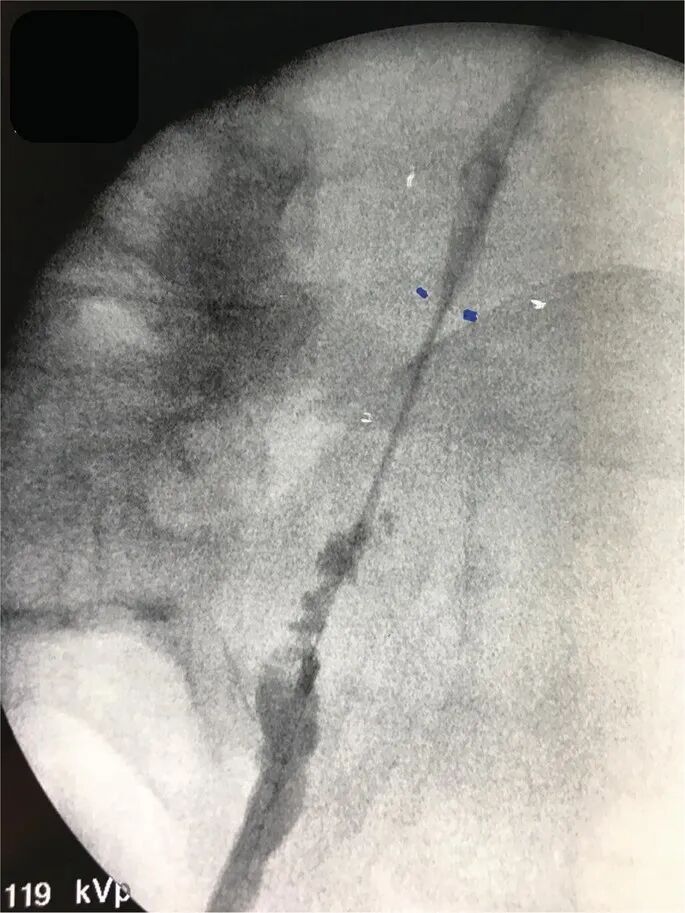

逆行肾盂造影显示输尿管粘膜呈手风琴样束,但未出现全层损伤,表现为缺乏造影剂外渗、全长输尿管通路保留以及上近端输尿管充盈。这些发现可诊断输尿管套叠,本病例是取石篮尝试取出一个相对较大的输尿管结石。